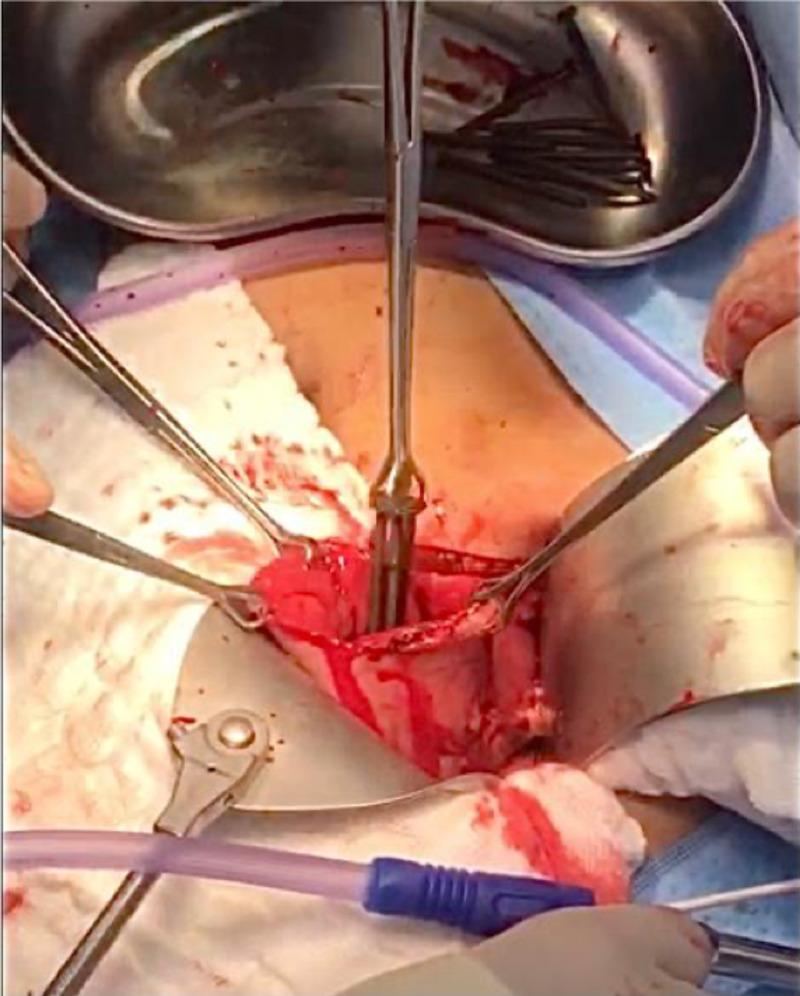

Ingestion of foreign bodies is common within the pediatric population; in adults, it occurs more commonly in those with a psychiatric background. Diagnosis of such cases can be readily made based on plain abdominal X-rays. As reported, many foreign bodies pass through the gastrointestinal tract without complications, obstruction, bleeding, and perforation. The ultimate decision of the best management approach for such cases should be made based on the available expertise as well as the patient's specific factors. Observation, endoscopic removal, and surgical intervention are all acceptable approaches in cases of metal foreign body ingestion. We report a case of a 29-year-old male patient brought to the emergency department following ingestion of multiple sharp nails. He underwent surgical exploration, which resulted in the retrieval of 73 metallic nails.

吞食异物在儿科人群中很常见;在成人中,吞食异物在有精神病史的人群中更为常见。此类病例的诊断可根据腹部平片轻松做出。据报道,许多异物可通过胃肠道而不出现并发症、梗阻、出血和穿孔。对于此类病例,最佳治疗方法的最终决定应基于现有的专业知识以及患者的具体因素。在金属异物吞食病例中,观察、内镜取出和手术干预都是可接受的方法。我们报告一例29岁男性患者,因吞食多根尖锐钉子被送往急诊科。他接受了手术探查,结果取出了73根金属钉子。